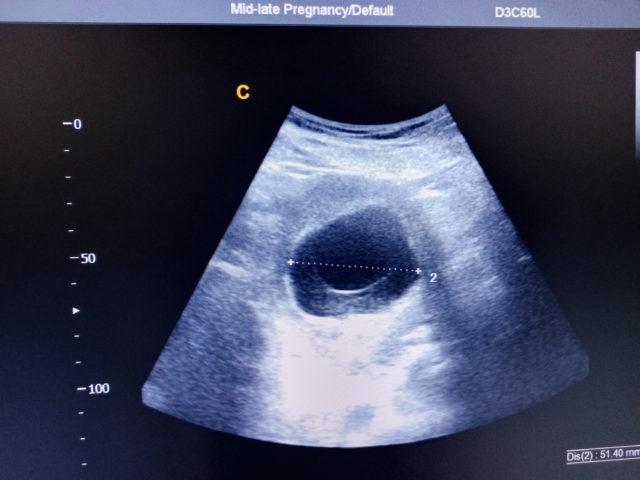

“Ini kemungkinan kehamilan kosong,” kata dokter menjelaskan apa yang dia lihat dalam foto USG.

Dalam bahasa medis, janin yang tidak berkembang itu disebut kehamilan kosong atau blighted ovum. Hal itu terjadi ketika sel telur yang dibuahi menempel di dinding rahim namun tak berkembang menjadi embrio.